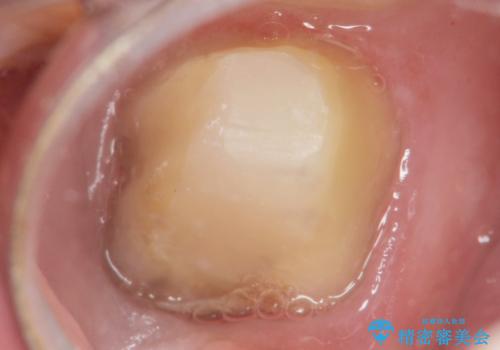

精査したところ、右下の一番奥の歯(右下7)に歯肉縁下に及ぶ深いう蝕を認めました。

神経がない歯であり痛みが出ないことから、自覚症状がほとんどなくう蝕が大きく進行してしまったと考えられます。

歯周外科処置(右下7遠心の骨整形及びディスタルウェッジ)により、深部に及ぶう蝕を除去するとともに歯肉縁上の健全歯質を獲得でき、適合の良い被せ物を作製することができました。